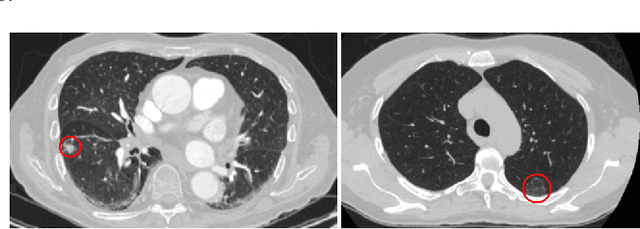

Abstract:Novel Coronavirus disease (COVID-19) is a highly contagious respiratory infection that has had devastating effects on the world. Recently, new COVID-19 variants are emerging making the situation more challenging and threatening. Evaluation and quantification of COVID-19 lung abnormalities based on chest Computed Tomography (CT) scans can help determining the disease stage, efficiently allocating limited healthcare resources, and making informed treatment decisions. During pandemic era, however, visual assessment and quantification of COVID-19 lung lesions by expert radiologists become expensive and prone to error, which raises an urgent quest to develop practical autonomous solutions. In this context, first, the paper introduces an open access COVID-19 CT segmentation dataset containing 433 CT images from 82 patients that have been annotated by an expert radiologist. Second, a Deep Neural Network (DNN)-based framework is proposed, referred to as the COVID-Rate, that autonomously segments lung abnormalities associated with COVID-19 from chest CT scans. Performance of the proposed COVID-Rate framework is evaluated through several experiments based on the introduced and external datasets. The results show a dice score of 0:802 and specificity and sensitivity of 0:997 and 0:832, respectively. Furthermore, the results indicate that the COVID-Rate model can efficiently segment COVID-19 lesions in both 2D CT images and whole lung volumes. Results on the external dataset illustrate generalization capabilities of the COVID-Rate model to CT images obtained from a different scanner.

Abstract:Lung diseases including infections such as Pneumonia, Tuberculosis, and novel Coronavirus (COVID-19), together with Lung Cancer are significantly widespread and are, typically, considered life threatening. In particular, lung cancer is among the most common and deadliest cancers with a low 5-year survival rate. Timely diagnosis of lung cancer is, therefore, of paramount importance as it can save countless lives. In this regard, deep learning radiomics solutions have the promise of extracting the most useful features on their own in an end-to-end fashion without having access to the annotated boundaries. Among different deep learning models, Capsule Networks are proposed to overcome shortcomings of the Convolutional Neural Networks (CNN) such as their inability to recognize detailed spatial relations. Capsule networks have so far shown satisfying performance in medical imaging problems. Capitalizing on their success, in this study, we propose a novel capsule network-based mixture of experts, referred to as the MIXCAPS. The proposed MIXCAPS architecture takes advantage of not only the capsule network's capabilities to handle small datasets, but also automatically splitting dataset through a convolutional gating network. MIXCAPS enables capsule network experts to specialize on different subsets of the data. Our results show that MIXCAPS outperforms a single capsule network and a mixture of CNNs, with an accuracy of 92.88%, sensitivity of 93.2%, specificity of 92.3% and area under the curve of 0.963. Our experiments also show that there is a relation between the gate outputs and a couple of hand-crafted features, illustrating explainable nature of the proposed MIXCAPS. To further evaluate generalization capabilities of the proposed MIXCAPS architecture, additional experiments on a brain tumor dataset are performed showing potentials of MIXCAPS for detection of tumors related to other organs.